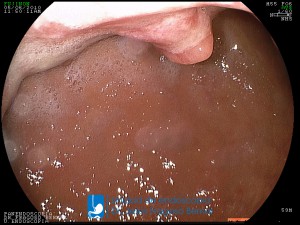

La Unidad de Endoscopía fue creada en 2002 por el Dr. Jesús Fragoso Bernal, es pionera en el estado por la utilización de la tecnología más avanzada, que nos permite ofrecer servicios integrales de diagnóstico y tratamiento para las enfermedades del aparato digestivo.